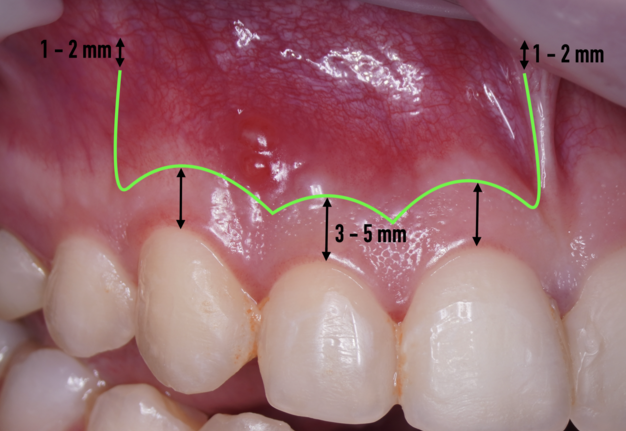

The most popular paramarginal or submarginal flap is the one designed by Clifford Ochsenbein and Raymond G. Luebke (1974) [4, 5]. The Ochsenbein-Luebke flap is formed by a scalloped horizontal sub-marginal incision placed within the attached gingiva, which follows roughly parallel to the contour of the gingival margin. The horizontal incision continues with two vertical releasing incisions [6]. These vertical incisions extend from a point 1 to 2 mm short of entering the mucobuccal fold to a point on the attached gingiva approximately 3 to 5 mm above or below the marginal gingiva and the sulcus depth (Figs 1 and 2) [7, 8].